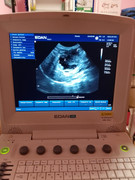

Здравствуйте, у кота по узи какое-то новообразование около поджелудочной, желчного и печени. Подскажите пожалуйста, на что это похоже? Есть только фото с экрана.

Здравствуйте! Очень сложно по картине понять, лучше короткое видео. Определяется образование неправильной формы, кистозной структуры, наиболее вероятно а поджелудочной железе, но объективно, нельзя исключить патологию желчных протоков.